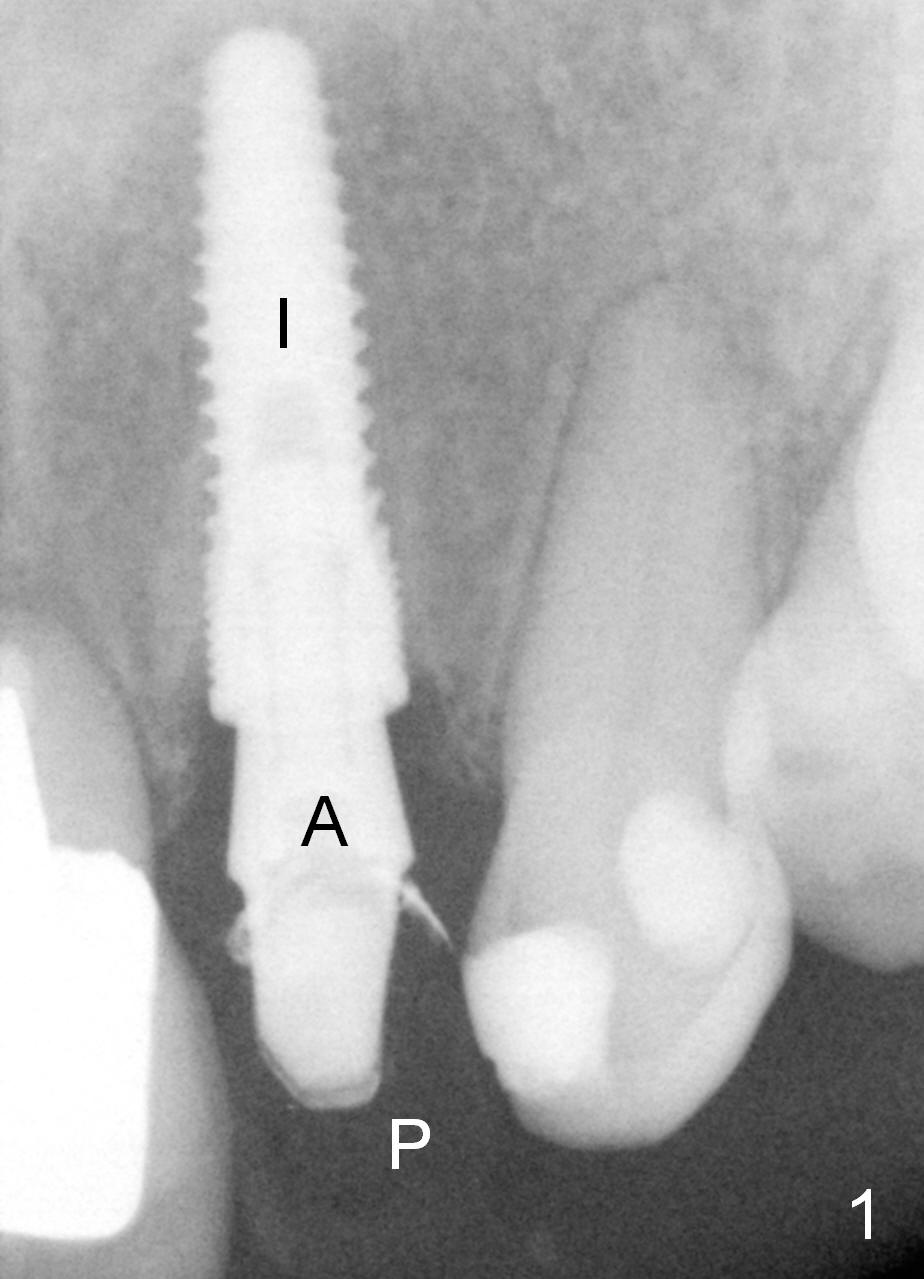

Placement of implant at the site of #10 is complicated. The trajectory is not ideal. Even though a 25 ° angled abutment is used, the abutment is still too buccal. Since the implant is placed deep (Fig.1,2), the margin is high (Fig.3). The margin of the crown should be thin and able to cover the Cavit as much as possible (Fig.3 C).

Fig.1,2 show the abutment (A) before and after torquing, respectively. After the torquing, the abutment turns mesially (Fig.2 white arrow) and apparently ascends slightly (black arrow).